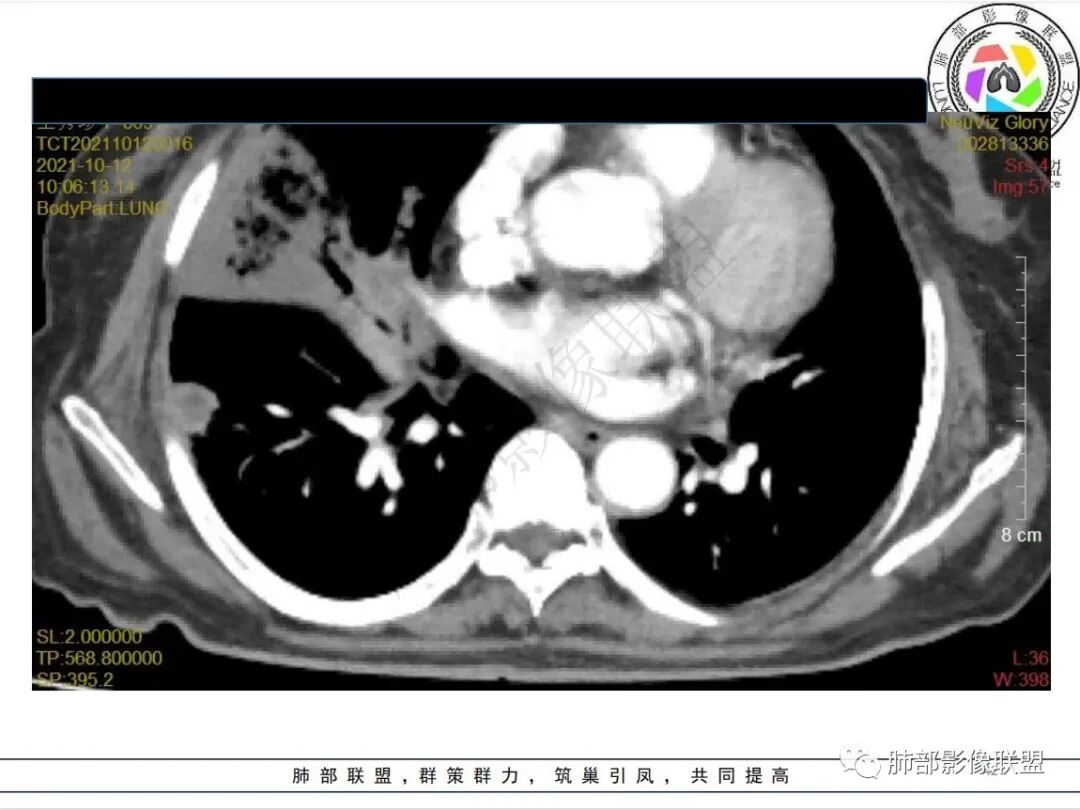

白血病化疗后,出现多发结节,边缘可见晕征,病灶内可见多发坏死,右肺中叶肺动脉可见充盈缺损,右肺中叶可见融冰征,考虑毛霉菌,右肺中叶肺动脉栓塞伴右肺中叶肺梗死。

4.白血病化疗后,CT上出现多发结节,边缘可见晕征,病灶内可见多发坏死,右肺中叶肺动脉可见充盈缺损,右肺中叶可见融冰征,右肺中叶肺动脉侵犯栓塞伴右肺中叶肺梗死,可符合真菌感染。

血管侵袭性曲霉病是最常见的类型,其特征是真菌菌丝侵入和阻塞中小肺动脉,形成凝固性坏死、肺泡出血或出血性梗死。

6.肺曲霉病典型的CT表现是结节周围有磨玻璃样的晕征表现,或胸膜为宽基底的楔形实变。晕征表现为曲菌感染的肺结节伴梗死和凝固性坏死,周围有肺泡出血。最终可出现空泡征象,并可观察到中央坏死组织与周围肺实质分离形成空气新月征。